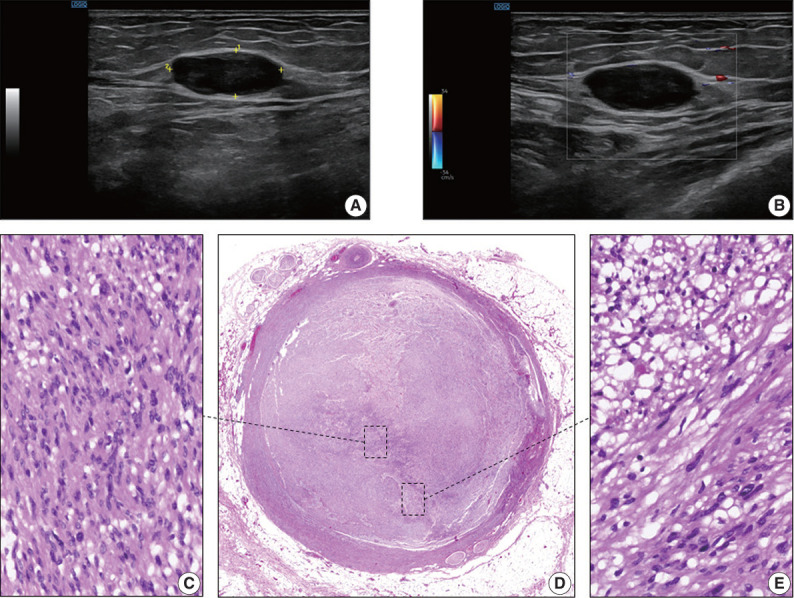

The blood vessel lumen is an extremely rare location for a benign peripheral nerve sheath tumor like schwannoma. Less than 10 cases have been previously reported. In this report, we present a case of a 68-year-old woman who had a soft tissue nodule at the posterior calf of her left leg during a physical examination. Pathological examination was performed after complete surgical excision. The patient underwent follow-up for 12 months after surgery without evidence of recurrence or any other complication. This is the first case of intravascular schwannoma reported as a cause of vein obstruction. Microscopically, the tumor was composed of Schwann spindle cells that were immunoreactive for S100 protein and SOX10. This tumor was surrounded by a well-defined vascular smooth muscle wall. Prospective series are required to improve the knowledge on the underlying mechanisms of intravascular schwannoma development.